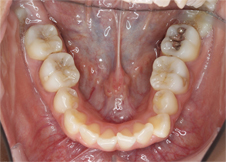

前歯のでこぼこと八重歯を気にされて来院されました。

左上の犬歯がかなり上から生えてきて八重歯になっています(左写真)。前歯の脇の歯は内側に入ってしまい前歯がでこぼこで、どちらの歯も磨きにくく汚れがたまりやすい状態です。

特に八重歯の状態は他の歯より上に位置するため磨き残されやすく、虫歯にしてしまいがちなので要注意です。

<治療開始前>

左上の犬歯が八重歯になっており、そのため上真ん中は大きく左へズレています。また本来、上の前歯は下の前歯に覆いかぶさらないといけないのですが、上下前歯は咬み合っていません。

<治療開始6ヶ月後>

歯が並ぶスペースが著しく不足しているためこれを解消すること、また上下の咬み合っていない前歯の状態を解消するために上下とも抜歯を行い治療を開始しました。治療開始から6ヶ月後、八重歯は改善しています。この後、上下の噛み合わせの改善を行いました。

<矯正治療後>治療期間22ヶ月

22ヶ月後、歯の移動を終了して装置を除去、保定に入りました。装置は表側の装置ですが目立ちにくいタイプのもの使用しています。材質はサファイアで透明度が高いため歯の色と馴染むのが特徴です。ワイヤーはホワイトワイヤーを使用してさらに目立ちにくくしています。